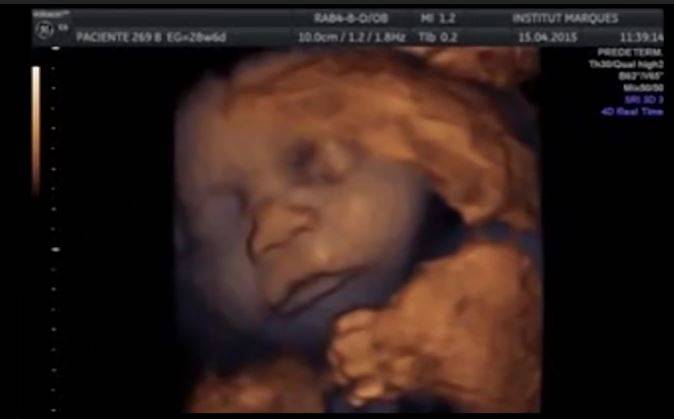

Bebè nel pancione con la musica (Screenshot video Institut Marquès)

Uno studio scientifico condotto dall’Institut Marquès, presentato presso l’Istituto Karolinska e l’Università di Stoccolma, ha esaminato gli effetti della musica sui feti tra la 14a e la 39a settimana di gestazione, nell’ambito di una ricerca sull’udito del feto e sull’effetto della musica all’inizio della vita.

Per studiare la reazione dei bebè alla musica nel pancione della mamma ed essere sicuri che il bambino percepisse il suono alla massima intensità, i ricercatori hanno creato un particolare dispositivo intravaginale che trasmettesse il suono una sorta di Babypod, come è stato chiamato, che emette onde sonore fino a 54 decibel. La musica fatta ascoltare ai bebè è la Partita in la minore per flauto solo – BWV 1013 di Johann Sebastian Bach.

Facendo ascoltare Bach ai bebè nel pancione, tramite il dispositivo intravaginale, i ricercatori hanno scoperto con l’ecografia in 3D che i bambini si muovono, spostano la testa, agitano le braccia e tirano fuori la lingua. Insomma, la musica sembra piacere ai nascituri, secondo gli studiosi. L’87% di loro ha reagito con movimenti della testa, degli arti, della bocca e della lingua, movimenti che si sono fermati quando i bambini non hanno sentito più la musica.Il 50% dei bambini, invece, ha aperto molto la bocca tirando fuori tutta la lingua.